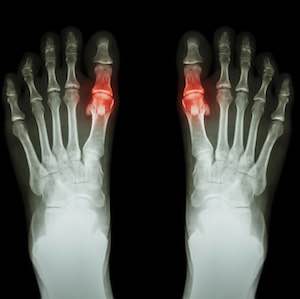

Krystaly kyseliny močové se usazují zejména v kloubech a šlachách, ale mohou se ukládat i ve vnitřních orgánech, především v ledvinách. V těchto místech mohou uvíznout a svým ostrým hrotem se zabodávat, čímž způsobují řadu komplikací.

- Intenzivní bolest kloubů: Dna se projevuje především silnou bolestí některých kloubů, ke které dochází nejčastěji v noci a brzy ráno. Postižen bývá hlavně palec u nohy, ale dna může zasáhnout i klouby rukou, kotníků a kolenou.

- Zarudnutí a otok kloubů: Oblast v okolí postižených kloubů bývá zarudlá, oteklá a citlivá na dotek. Kůže na kloubu je lesklá a napnutá.

- Omezená pohyblivost: Neléčená dna může vést k deformaci kloubu a zánětu, což má za následek potíže s hybností.